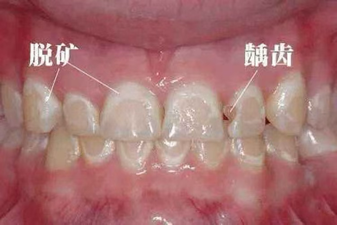

第1阶段:牙釉质“悄悄脱矿”。

表现:牙齿表面出现白色或浅褐色斑点(像粉笔痕),不疼不痒。

原因:牙菌斑中的细菌分解食物残渣,产生酸性物质,腐蚀牙釉质(牙齿最外层)。

第2阶段:牙釉质被“攻破”。

表现:白斑变黑,形成小蛀洞(可能塞食物),冷热敏感。